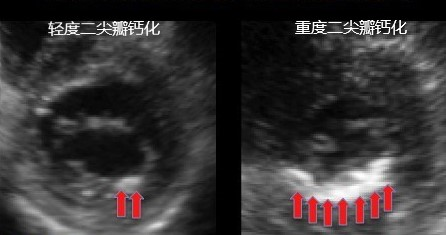

二尖瓣瓣环钙化是钙沉积逐步沉积于二尖瓣瓣环上的慢性病变。二尖瓣瓣环本身一个柔软的富有弹性的纤维环,逐步钙化过程使其变得僵硬。二尖瓣瓣环钙化通常发生于后瓣环。绝大多数人的钙化并不会影响二尖瓣功能,因此不需要治疗。但当二尖瓣环的钙化使二尖瓣瓣膜应力增加时,会使二尖瓣启闭受到影响,导致血流动力学不稳定。也就是说长年累月的使用,我们的门框生锈了,我们的房门打开和关闭都收到影响了。

怎么样才能知道自己是否有二尖瓣瓣环钙化?

超声心动图是最主要的诊断方式。此外,CT和MRI也可对其进行诊断。特别严重的钙化,通过胸片亦可诊断。